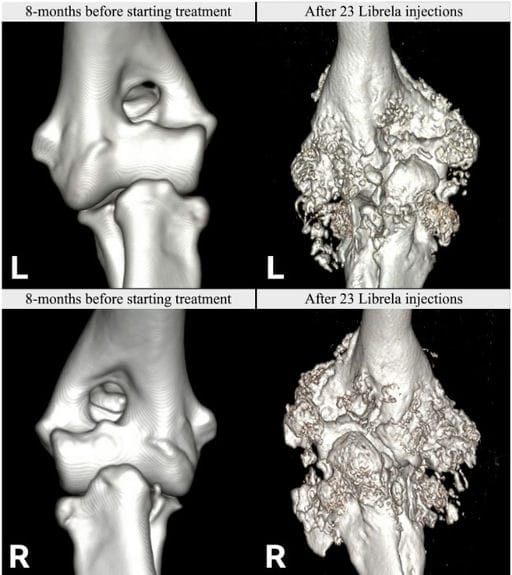

Left (L): Normal pre-treatment CT scans from Case 11, a 7.5-year-old Labrador Retriever. Post-Librela CT scans revealing fulminant periarticular osteophytosis. Right (R): Post-Librela CT scans revealing fulminant periarticular osteophytosis. AER: The attending specialist filed an AER to the VMD specifying their suspicion of RPOA. This report was shared with the MAH, who filed an AER for non-serious arthritis, with an outcome of recovered/resolving (Supplementary Figure S5).